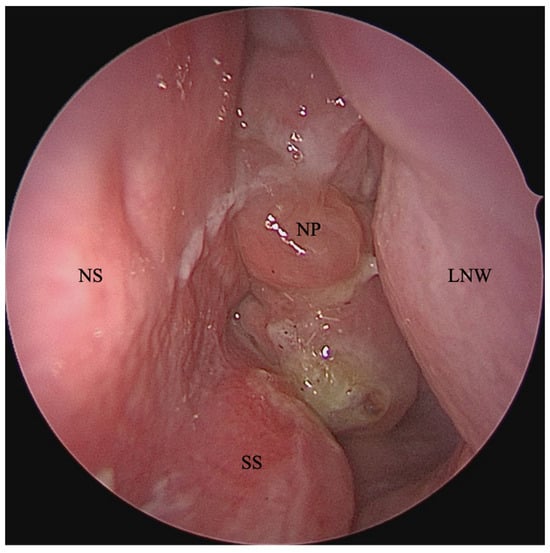

- Beswick, D.M.; Humphries, S.M.; Balkissoon, C.D.; Strand, M.; Vladar, E.K.; Lynch, D.A.; Taylor-Cousar, J.L. Impact of Cystic Fibrosis Transmembrane Conductance Regulator Therapy on Chronic Rhinosinusitis and Health Status: Deep Learning CT Analysis and Patient-reported Outcomes. Ann. Am. Thorac. Soc. 2022, 19, 12–19. [Google Scholar] [CrossRef]

- Beswick, D.M.; Humphries, S.M.; Miller, J.E.; Balkissoon, C.D.; Khatiwada, A.; Vladar, E.K.; Ramakrishnan, V.R.; Lynch, D.A.; Taylor-Cousar, J.L. Objective and patient-based measures of chronic rhinosinusitis in people with cystic fibrosis treated with highly effective modulator therapy. Int. Forum Allergy Rhinol. 2022, 12, 1435–1438. [Google Scholar] [CrossRef]